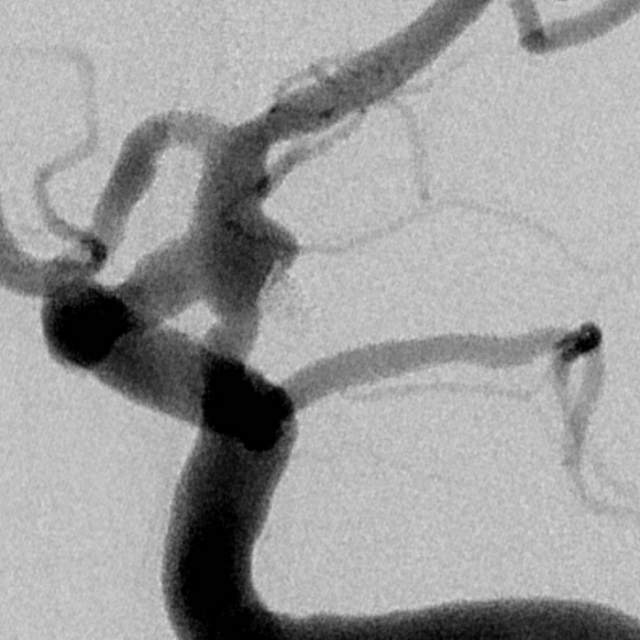

近日,老人家恢复了差不多了,为了防治日后宽颈的脑动脉瘤复发,还需要稍微进行一下修修补补,减少血流对薄弱的脑动脉瘤的冲击,那就需要再简单加固一下。

这个加固的材料呢,放进血管后,慢慢会被自己的内皮细胞覆盖,变成自己身体的一部分,还能防止动脉瘤复发,是一个非常好的装备。

装备虽好,那还的找靠谱的医生给安装进去吧。今日,我们顺利为老人家在病变部位的血管植入了血流导向装置,手术顺利。然而,不是每一个破裂的脑动脉瘤患者像老人家一样这么幸运,能够有机会赶到医院,得到及时的治疗……